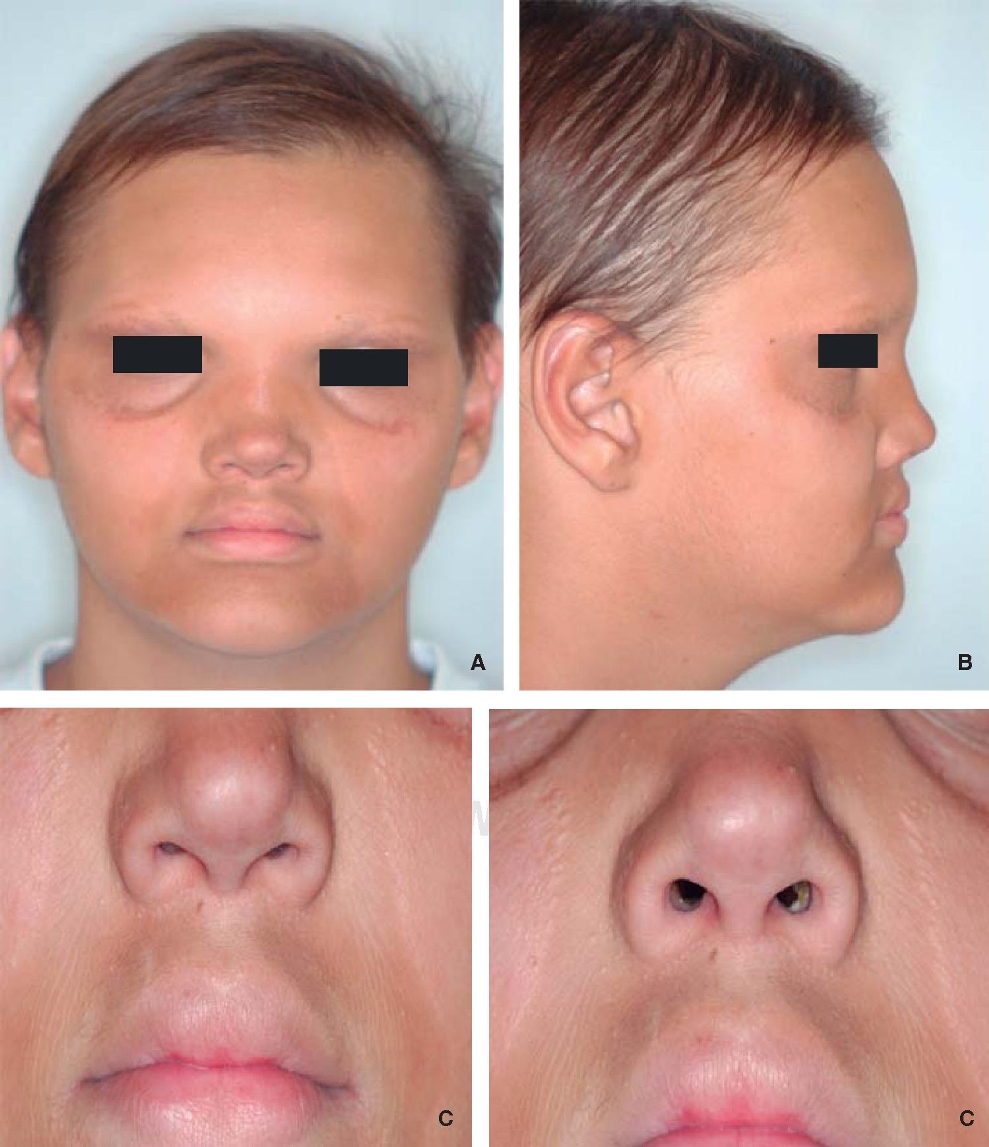

Durante la anamnesis se refirió presencia continua de hipertermias, de origen desconocido y ausencia de piezas dentarias. En el examen clínico se identificó hipohidrosis con la piel delicada y seca, secreción lagrimal disminuida; cabellos, pestañas y cejas escasas y muy finas (hipotricosis); puente nasal y labios prominentes, frente prominente, presencia de arrugas periorbitarias y perioral; hiperpigmentación periorbital y perioral, nariz pequeña con hipoplasia de narinas (Figura 1).

Figura 1. Signos característicos de DEH. A. Se puede observar cabellos y cejas escasas, hiperpigmentación perioral y periorbital. B. Se muestra puente nasal y labios prominentes. C. Arrugas perioral y periorbitales.